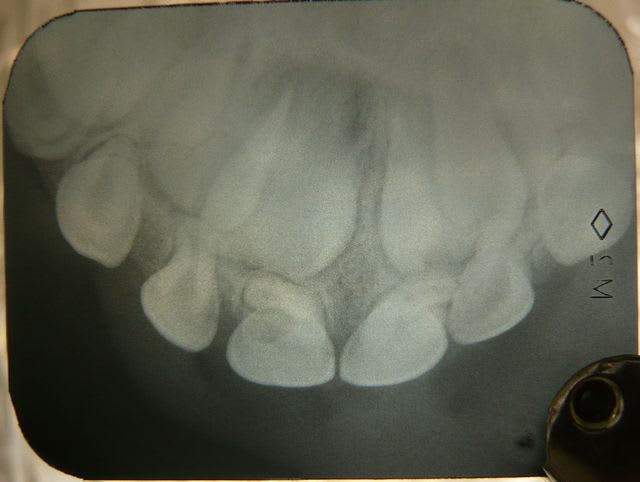

cas de sophie 8 ans au 1er RV

à l'interrogatoire il semble qu'il y ait eu chute vers 3 ans

la dent est restée assymptomatique

personne ne s'est inquiété de la difference de taille entre 11 et 61...

ça descend...lentement